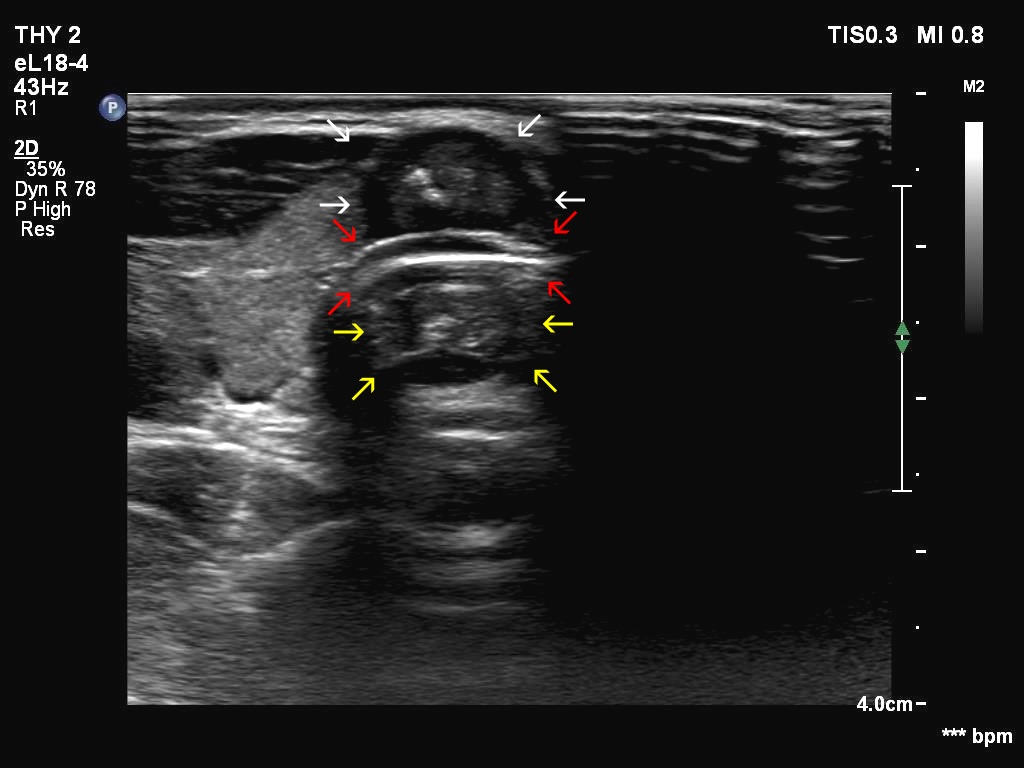

Introduction - case 745 (ultrasonographic picture 6b)

Isthmus, transverse scan. The nodule ventral to the trachea is marked with white arrows, the complex wall of the trachea is with red arrows. The structure dorsal to the trachea (yellow) arrows is the mirror image artifact of the nodule.